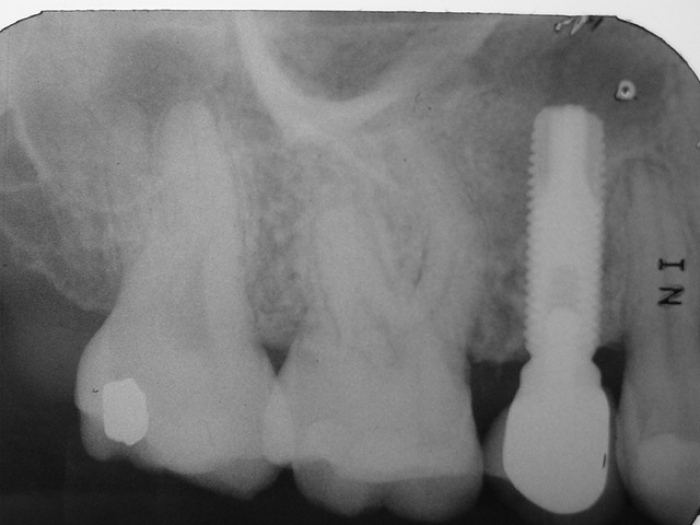

Raio X inicial